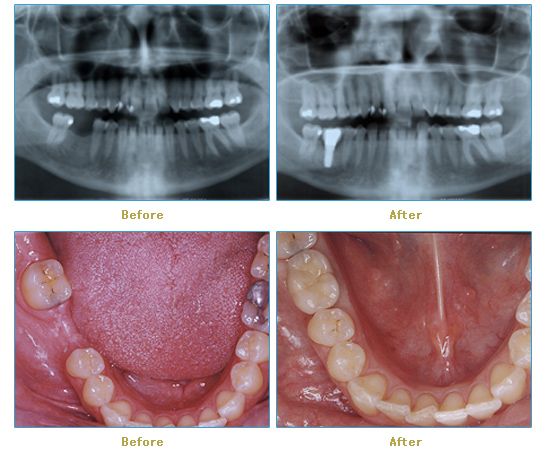

Dr. Cabianca has restored hundreds of smiles through the latest techniques in restorative and cosmetic dentistry. The following before and after photos document a few such cases in which Dr. Cabianca has replaced and reshaped teeth to produce wonderful smiles. Click on any of the images below to view larger versions of the photos.